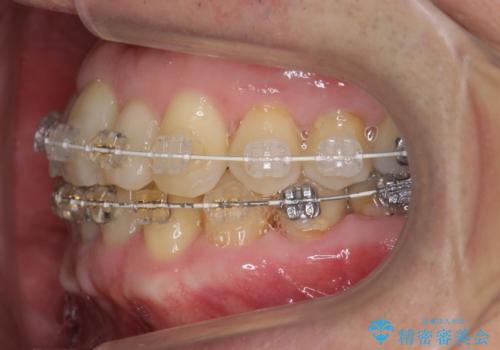

- 矯正装置

- 審美装置

- 治療期間

- 3年6ヶ月

- 治療回数

- 30回以上

右上の八重歯は、右上の奥歯を矯正用ミニスクリューを用いて遠心移動を行い解消しました。

下の前歯はIPR(エナメル質を薄く削り歯を小さくする処置)を行なっています。